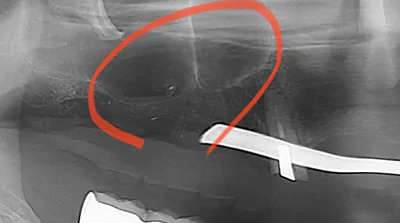

サイナスリフト

骨の厚みが非常に少ない場合や、複数の歯を失っている場合に行う方法です。歯が生えていた部分の側面から歯ぐきを切開し、骨に小さな穴を開けます。その奥にある「上顎洞(じょうがくどう)」を覆うシュナイダー膜を傷つけないように慎重に持ち上げ、そのスペースに自家骨や人工骨を移植します。移植した骨が定着するまで約3ヶ月~6ヶ月待ってから、インプラントを埋入します。外科的な処置のため高い技術が求められます。

症例